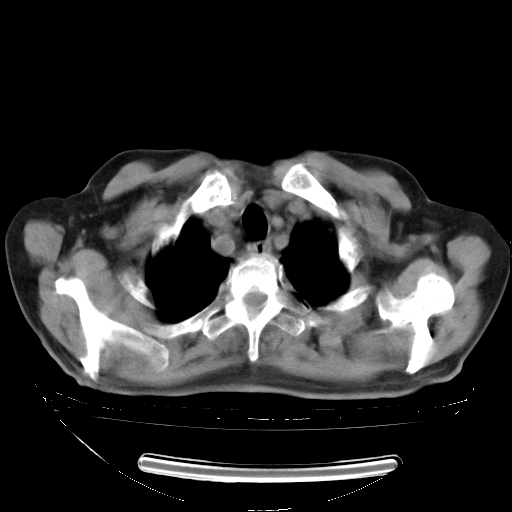

今天复查肺部CT,发现双肺广泛磨玻璃样改变。所以我把3月19日和5月9日相隔50天的肺部CT上传。请大家会诊。

2009年3月19日肺部CT片。

2009年3月19日肺部CT